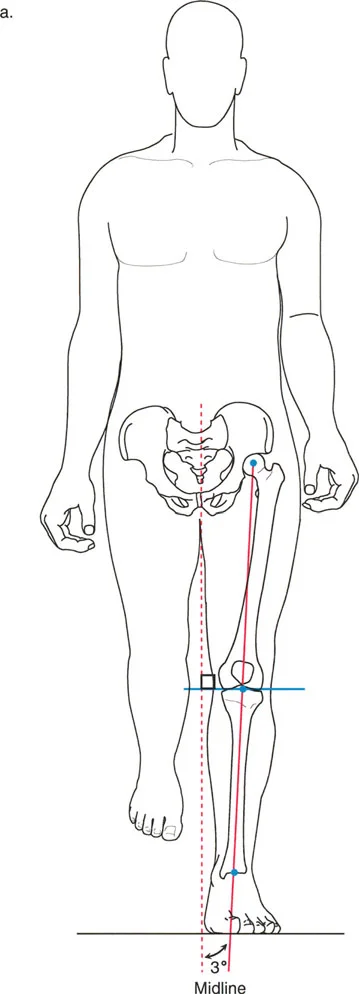

حركية المشي

عند المشي، لا نبقي أقدامنا متباعدة بعرض الكتفين. بل نضع قدماً أمام الأخرى على طول مسار خط المنتصف. خلال مرحلة الوقوف على ساق واحدة أثناء المشي، تكون الساق التي تحمل الوزن مائلة (مقربة) إلى الخط العمودي بحوالي 3 درجات.

ولأن الزاوية الفخذية البعيدة الوحشية الميكانيكية (mLDFA) هي حوالي 87 درجة والزاوية الظنبوبية القريبة الإنسية الميكانيكية (MPTA) هي حوالي 87 درجة، فإن هذا الانحراف المدمج بمقدار 3 درجات يلغي تماماً الميلان بمقدار 3 درجات للساق أثناء المشي. وهذا يسمح لخط مفصل الركبة بالحفاظ على توجيه مثالي وموازٍ للأرض أثناء المشي. يضمن خط المفصل الموازي للأرض تقليل قوى القص وتوزيع قوى الضغط بالتساوي عبر الأجزاء الداخلية والخارجية من الركبة.

هذا التكيف البيوميكانيكي الرائع هو ما يسمح لنا بالمشي بكفاءة ودون ألم. عندما يتم فقدان هذا التوازن بسبب تشوه أو إصابة، تظهر المشاكل. الأستاذ الدكتور محمد هطيف، بخبرته العميقة في بيوميكانيكا الحركة، يهدف إلى استعادة هذا التوازن الدقيق لمرضاه، مما يمكنهم من استعادة نمط المشي الطبيعي والعيش بحرية من الألم.